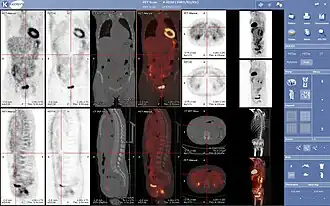

PET/CT je diagnostická zobrazovací metoda spojující vyšetření počítačovou tomografií (CT) a pozitron emisní tomografií (PET). Získané obrazy obsahují jak poměrně podrobnou informaci o anatomické stavbě, tak i informaci o metabolické aktivitě tkání.